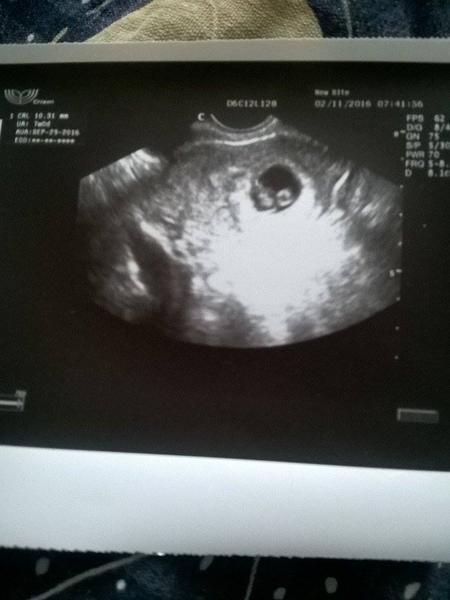

@paulittav Jeee, ty jsi hodna, ze na me myslis! Zatim vsechno zustava stejne, tak to vypada nadejne...na gynde jsem jeste nebyla, v pondeli se tam planuju objednat, jestli se do te doby neco nepodela...na testu dalnice, tak silny carky jsem minule vubec nemela, tak z toho mam lepsi pocit. A pak uvidime na utz, co tam bude/nebude a hlavne KDE 🙂 Nevim, kdy prijde ten moment, ze radost bude prevazovat nad strachem. Par tydnu jeste asi ne no 🙂 Tak prosim drz pesti!